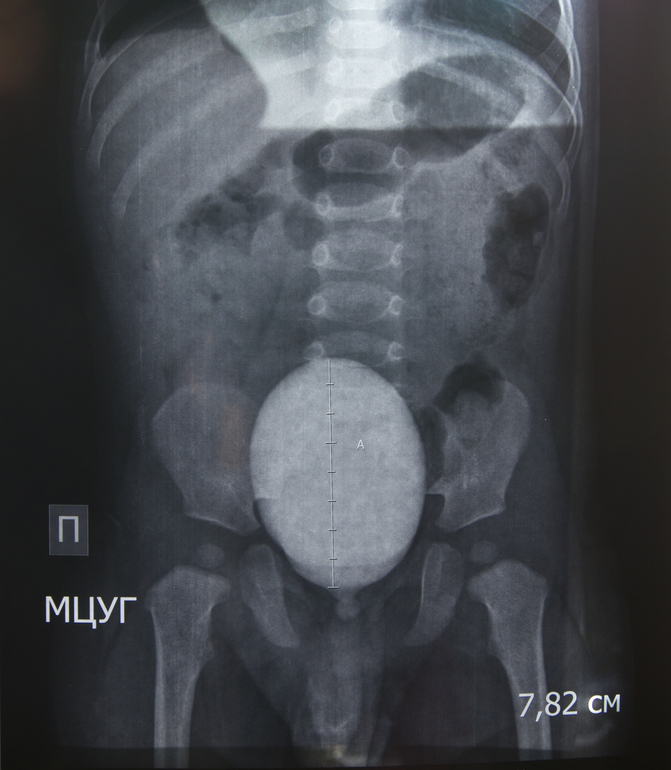

Ситуация 1: ребенку 1 год и 3 мес, в год прошли обследование (в/в уро- и цистография с контрастом), был поставлен диагноз "левосторонний гидронефроз 1 ст, фимоз". На апрель назначена операция по удалению крайней плоти. Нефролог говорит, что пока основной причиной гидронефроза признается именно фимоз. Дополнительных исследований (например, доплерография сосудов почек) не назначалось. Мой вопрос заключается в том, как часто (если таковое вообще возможно) фимоз может стать исключительной причиной гидронефроза? Если дело только в нем, операция окажется оправданной, если же препятствие в другом месте, ребенку предстоят "лишние" испытания, ведь вероятность того, что физиологический фимоз пройдет сам, высока. Для полноты картины я могу предоставить оцифровку рентгеновских снимков и выписку из истории болезни.

Если возможно, не могли бы Вы оценить результаты рентгенографического обследования моего младшего сына? На сколько качественно, на Ваш взгляд, были сделаны снимки? Согласно заключению нефролога, рефлюкс исключен. Если есть стриктура мочеточника (любой этиологии), должна ли она визуализироваться на рентгеновском снимке, или бывают случаи, которые проще диагностировать на УЗИ с диуретиком?